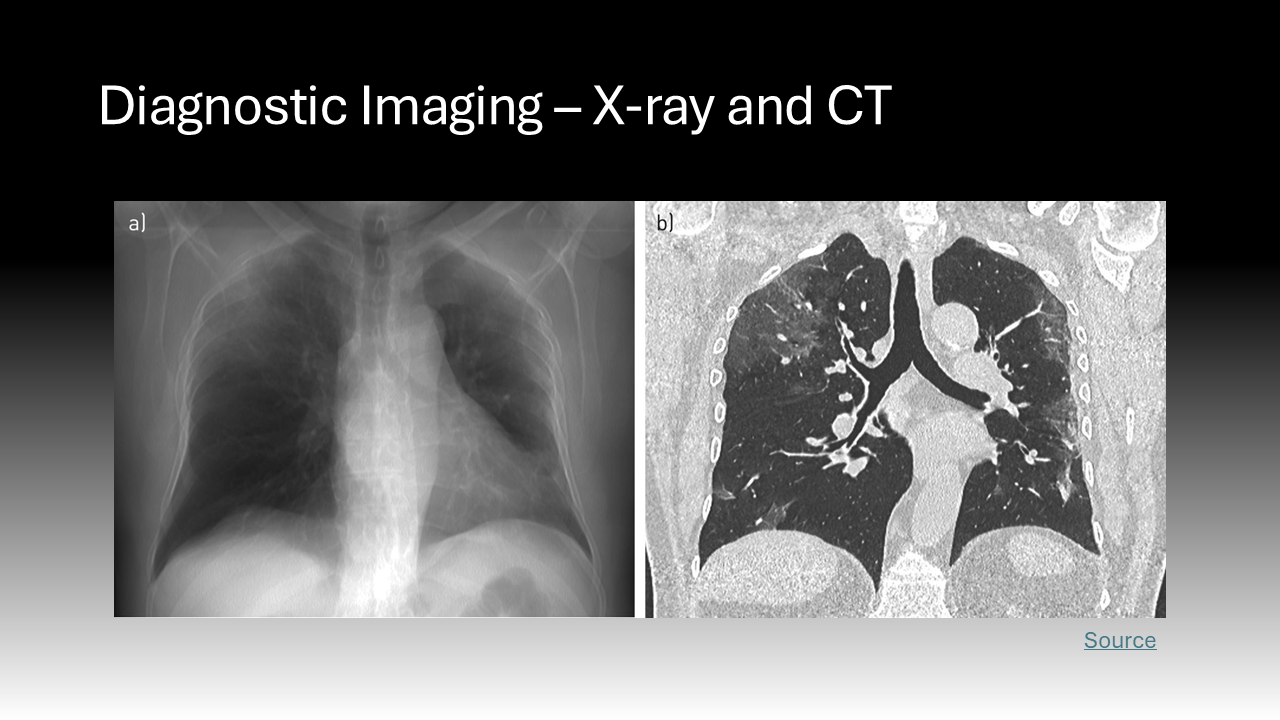

Ionizing radiation encompasses all high-energy rays that detach electrons from atoms. The body absorbs a fraction of this energy, which is disruptive at the molecular level.2 Ionizing radiation is found at low levels in the natural environment but has been employed at higher doses in medicine since the late 19th century.3 X-rays are ubiquitous in healthcare; this ionizing radiation has been the basis of two-dimensional diagnostic images and CT scans for years but is now employed during procedures.3 Cardiologists, neurosurgeons, orthopedic and vascular surgeons, and interventional radiologists all use live, continuous fluoroscopic imaging intraoperatively for “real-time feedback” during procedures.4 This technology not only allows for more accurate interventions but enables the use of minimally invasive approaches that replace open surgeries.4 In sum, the expanding use of X-ray technology in medicine, especially over the past 20 years, has led to more efficient diagnosis and treatment that is safer and more tolerable for patients.5 However, it also exposes a more diverse number of physicians to radiation and its harmful effects.5 Whereas X-rays during a diagnostic image or cancer radiation treatment are delivered to a physically isolated patient, physicians must be in close proximity to patients and radiation sources to perform procedures.5 This creates the current dilemma where healthcare providers now comprise the largest group of workers exposed to radiation in the world.5